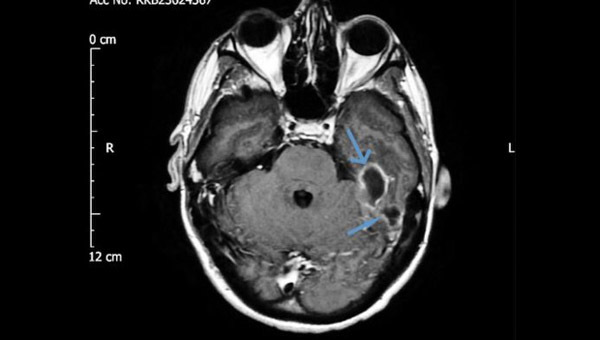

Khi đến bệnh viện, người đàn ông được chụp CT não. Các hình ảnh cho thấy có hai ổ áp xe, các khu vực bị viêm chứa đầy mủ, trong xương ở đáy hộp sọ, liền kề với ống tai trái của bệnh nhân.

Hình ảnh chụp CT cho thấy vùng nhiễm trùng của người đàn ông

Người đàn ông được chẩn đoán bị viêm tai giữa hoại tử externa. Các bác sĩ cho biết, ổ nhiễm trùng bắt nguồn từ trong tai trái và lan dần sang các khu vực xung quanh. Anh ta đã bị nhiễm vi khuẩn nghiêm trọng bắt đầu từ ống tai, tiến vào xương dưới đáy sọ và sau đó di chuyển lên trên, vào màng não.